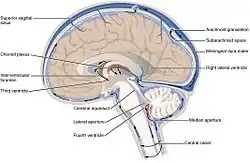

![]() Image showing the location of CSF highlighting the brain's ventricular system | |

In humans, there is about 125–150 mL of CSF at any one time.[1] This CSF circulates within the ventricular system of the brain. The ventricles are a series of cavities filled with CSF. The majority of CSF is produced from within the two lateral ventricles. From here, CSF passes through the interventricular foramina to the third ventricle, then the cerebral aqueduct to the fourth ventricle. From the fourth ventricle, the fluid passes into the subarachnoid space through four openings – the central canal of the spinal cord, the median aperture, and the two lateral apertures.[1] CSF is present within the subarachnoid space, which covers the brain and spinal cord, and stretches below the end of the spinal cord to the sacrum.[1][2] There is a connection from the subarachnoid space to the bony labyrinth of the inner ear making the cerebrospinal fluid continuous with the perilymph in 93% of people.[3]

CSF moves in a single outward direction from the ventricles, but multidirectionally in the subarachnoid space.[4][3] The flow of cerebrospinal fluid is pulsatile, driven by the cardiac cycle.[5] The flow of CSF through perivascular spaces in the brain (surrounding the cerebral arteries) is obtained through the pumping movements of the walls of the arteries.[5]